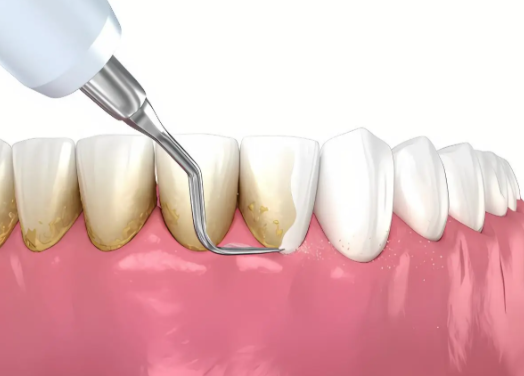

1. 日常清洁:种牙后要像爱护天然牙一样做好日常清洁,每天早晚正确刷牙,使用牙线等清洁工具。保持口腔卫生,能有效预防种植体周围炎等问题。

2. 定期复查:要定期到医院进行专精维护,一般每3 - 6个月复查一次。医生会检查种植牙的情况,及时发现并处理问题。